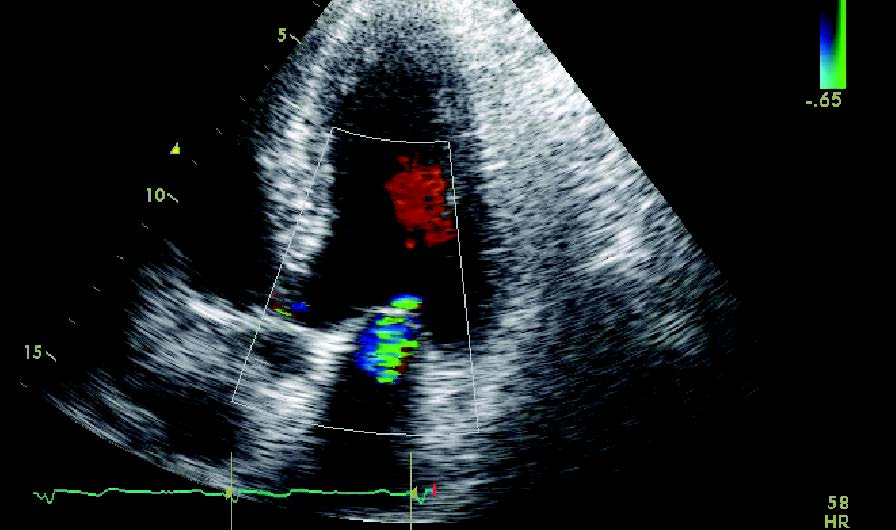

位于李树培院15楼的心导管及介入治疗中心(CCIC)添置了不少高科技仪器如数码平板血管造影系统、血管内腔超声波系统及最新3D光学相干断层扫描,为病人提供心脏介入检查,以了解心血管状况,协助医生作出准确诊断和适当治疗。

高科技仪器 本中心添置最新、最先进的仪器,全面配合优质的诊断及治疗服务: